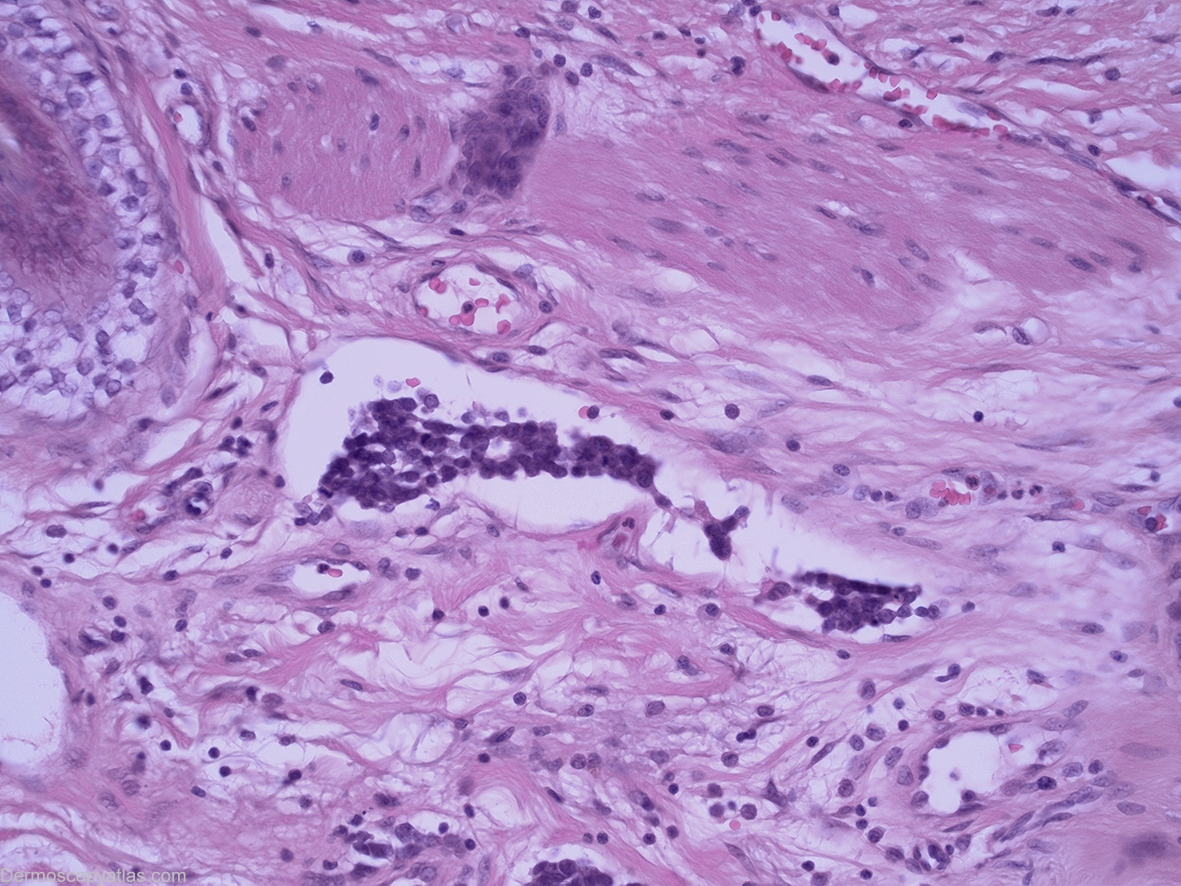

Image Number #2841 (Merkel cell carcinoma)

Site: Scalp

Diagnosis: Merkel cell carcinoma

History: This 83 year old gentleman presented for a routine skin check and this lesion was discovered. Prior to biopsy this lesion was lasered without biopsy by another practitioner but subsequent wide excision of the area discovered a residual dermal based Merkel cell carcinoma at the site where this lesion had been.